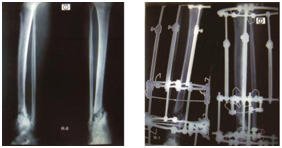

Figure 2: Case 2

1. Infected non union right lower tibia.

2. Radiograph of right tibia fibula with Ilizarov in situ (2nd Post-op).

3. Radiograph of right tibia fibula with Ilizarov in situ after 6 months follow up.

4. Final radiograph of tibia fibula after 8 months follow up.

5. Clinical appearance of the patient (Standing position).

6. Clinical appearance of the patient (sitting position).